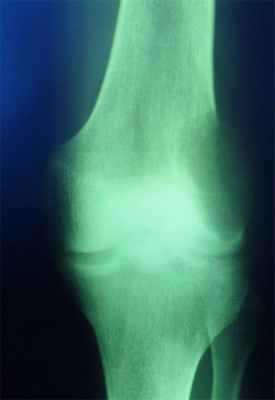

Гигантоклеточная опухоль

(остеобластокластома)

- состоит из клеток 2 типов- многоядерных гигантских и мелких одноядерных,

- поражаются люди в возрасте от 20 до 40 лет,

- локализация бедренная кость - дистальный конец, проксимальный конец б/берцовой кости, дистальный конец лучевой кости. Из плоских костей – тазовые кости и лопатка, очень редкая локализация в позвонках,

- одиночность и изолированность поражения,

- характерно расположение опухоли в эпиметафизраном отделе, который значительно вздут и деформирован, имеет вид крупнобугристого полушария, булавы,

- опухоль доходит до суставного хряща и обрывается,

- растет во всех направлениях, но главный рост происходит вдоль длинной оси кости в сторону с/3 диафиза кости,

- поперечник опухоли может увеличивать нормальный диаметр опухоли в 3-5 раз.

- ячеистый тип - опухоль состоит из отдельных камер, отделенных друг от друга полными и неполными перегородками (мыльные пузыри или неправильные соты),

- корковое вещество раздвигается, вздувается изнутри, истончается, надкостничных наслоений нет,

- при больших опухолях корковое вещество рассасывается и опухоль окружена со всех сторон тонкой скорлупой состоящая из стенок поверхностно расположенных ячеек.

- остеолитический тип – полное отсутствие ячеистого или трабекулярного рисунка, дефект кости вполне гомогенен,

- краевой блюдцеобразный дефект,

- корковый слой на пораженном месте рассасывается, а на границе с дефектом корка заострена, не подрыта и не имеет никаких периостальных наслоений,

- контуры дефекта резкие,

- патологические переломы в 12% случаев.